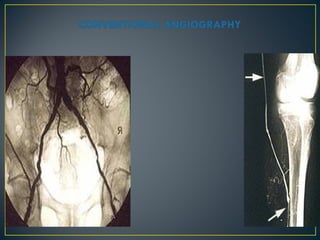

invasive

• CTA

• MRA

• Angio

• Requires iodinated contrast

• Requires ionizing radiation

• No ionizing radiation

• Noniodine–based intravenous contrast medium

rarely causes renal insufficiency or allergic

reaction

• Gadolinium use may cause nephrogenic

systemic fibrosis (NSF)